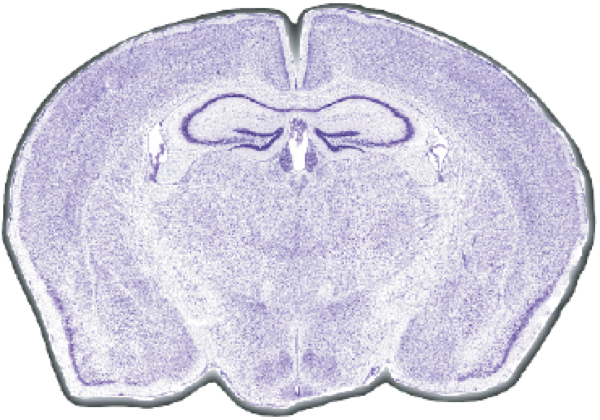

(Circa 2002) MiceSlice produces ultra high-resolution digital brain sections for standardized preparation of brain section tissues. Microscope image tiles are seamlessly reassembled into one brain section and then rotated to perfect alignment. This provides the foundation material for development of standardized experimental protocols.

MiceSlice provides ultra-high resolution digital brain sections from the standardized preparation of brain section tissues. Microscope image tiles are seamlessly reassembled into one brain

section and rotated to perfect alignment. MiceSlice provides the foundation material for the development of standardized experimental protocols. The rigorous quality control applied to

MiceSlice technology makes this the "gold standard" in histological preparations of rodent brain tissue.